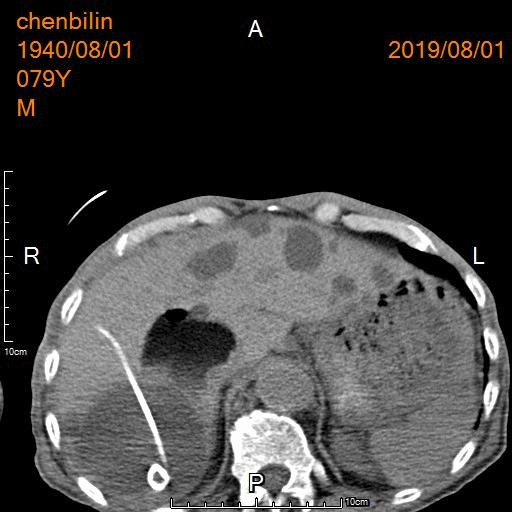

CT引导下肝囊肿穿刺置管引流治疗

再次行另一较大肝囊肿穿刺置管引流及硬化治疗